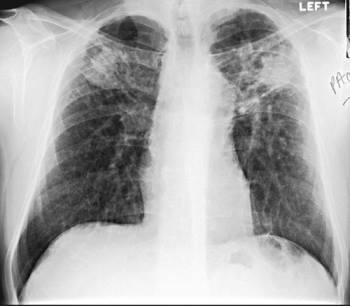

Dois sinais que podem aparecer no Rx de tórax de TEP?

Sinal de Westermark

Oligoemia localizada (+ preto)

Sinal/corcovas de Hampton

Hipotransparência triangular periférica